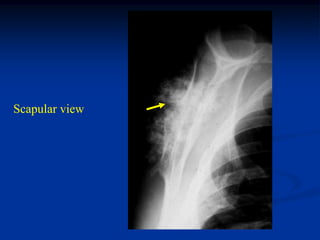

Case #567

28 year female

enchondroma scapula